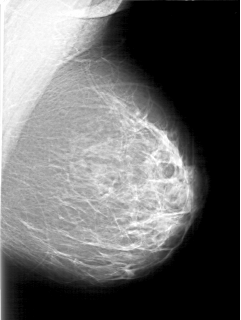

D_4197_1.LEFT_CC

LEFT_CC LINES 5461 PIXELS_PER_LINE 3601 BITS_PER_PIXEL 12 RESOLUTION 43.5 NON_OVERLAY